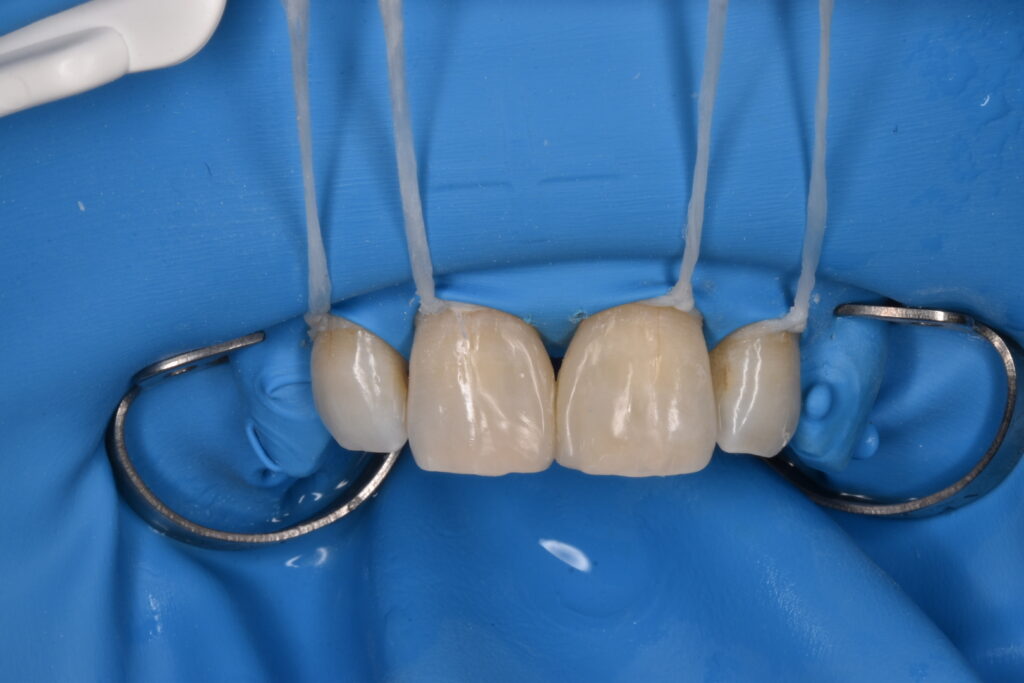

施術中

ダイレクトボンディングの治療は必ずラバーダム防湿を行います。局所麻酔をして行うため痛みはありません。

*他院で行われたダイレクトボンディングの除去はかなり大変です。除去費用として1歯税別5000円頂いております。歯を削らずマイクロスコープを使用して丁寧に除去するためです。